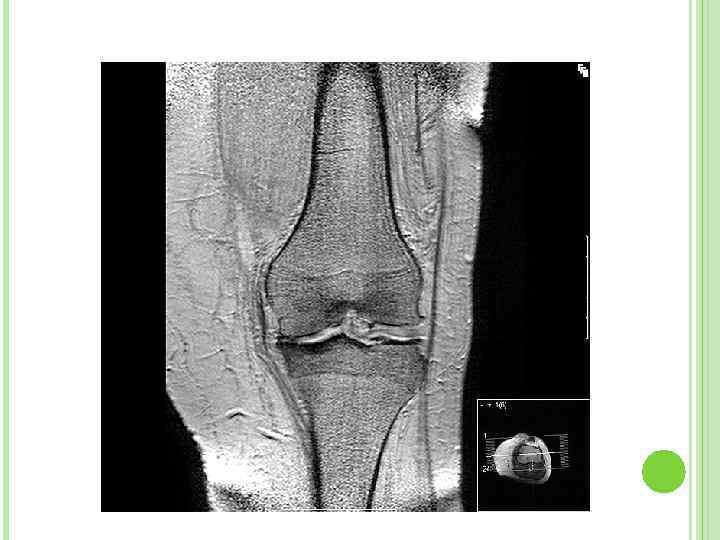

ДИАГНОЗ Незначительное повышение остеофазовых показателей. Рентген: разрастание костей (остеофиты).

АРТРОЗЫ заболевания, в основе которых лежит обменно дистрофический процесс, выражающийся в процессах атрофии хряща, разрежении костной ткани (остеопороз), новообразование костной ткани, отложениях солей кальция в околосуставной ткани, связки, капсулу сустава. Деформмрюущий остеоартроз.

ДЕФОРМИРУЮЩИЙ ОСТЕОАРТРОЗ дегенеративно дистрофическое заболевание суставов, причиной которого является поражение хрящевой ткани суставных поверхностей. Дегенерация суставного хряща – физиологическое явление после 60 лет в 100%.

ОСОБЕННОСТИ БОЛЕЙ появляется или усиливается при нагрузке к вечеру; уменьшается или проходит в покое; локализация; движения малоболезненны и малоограничены в суставах; нет выраженности обострения, течение постепенное; деформация дистальных межфаланговых суставов. При коксартрозе нарушается походка вследствие укорочения ноги за счет сплющивания головки бедра – атрофия мышц бедра. При поражении коленного сустава отмечается хруст сустава, во время движения.